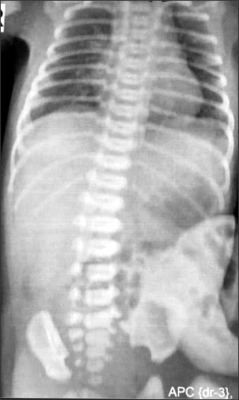

Fig. 1). The nasogastric tube was draining bile. An abdominal radiograph revealed few bowel loops inside the sac (

Fig. 2). The baby was taken up for surgery after adequate resuscitation. Intra-operatively, the sac contained few loops of small intestine. There was a fusiform SDI, about 25 cm proximal to the ileocecal valve. Note was made of conspicuous mesenteric vessels or mesenteric folds in a V-shaped pattern towards the two ends of the SDI (

Fig. 2An abdominal radiograph shows few bowel loops inside the sac.